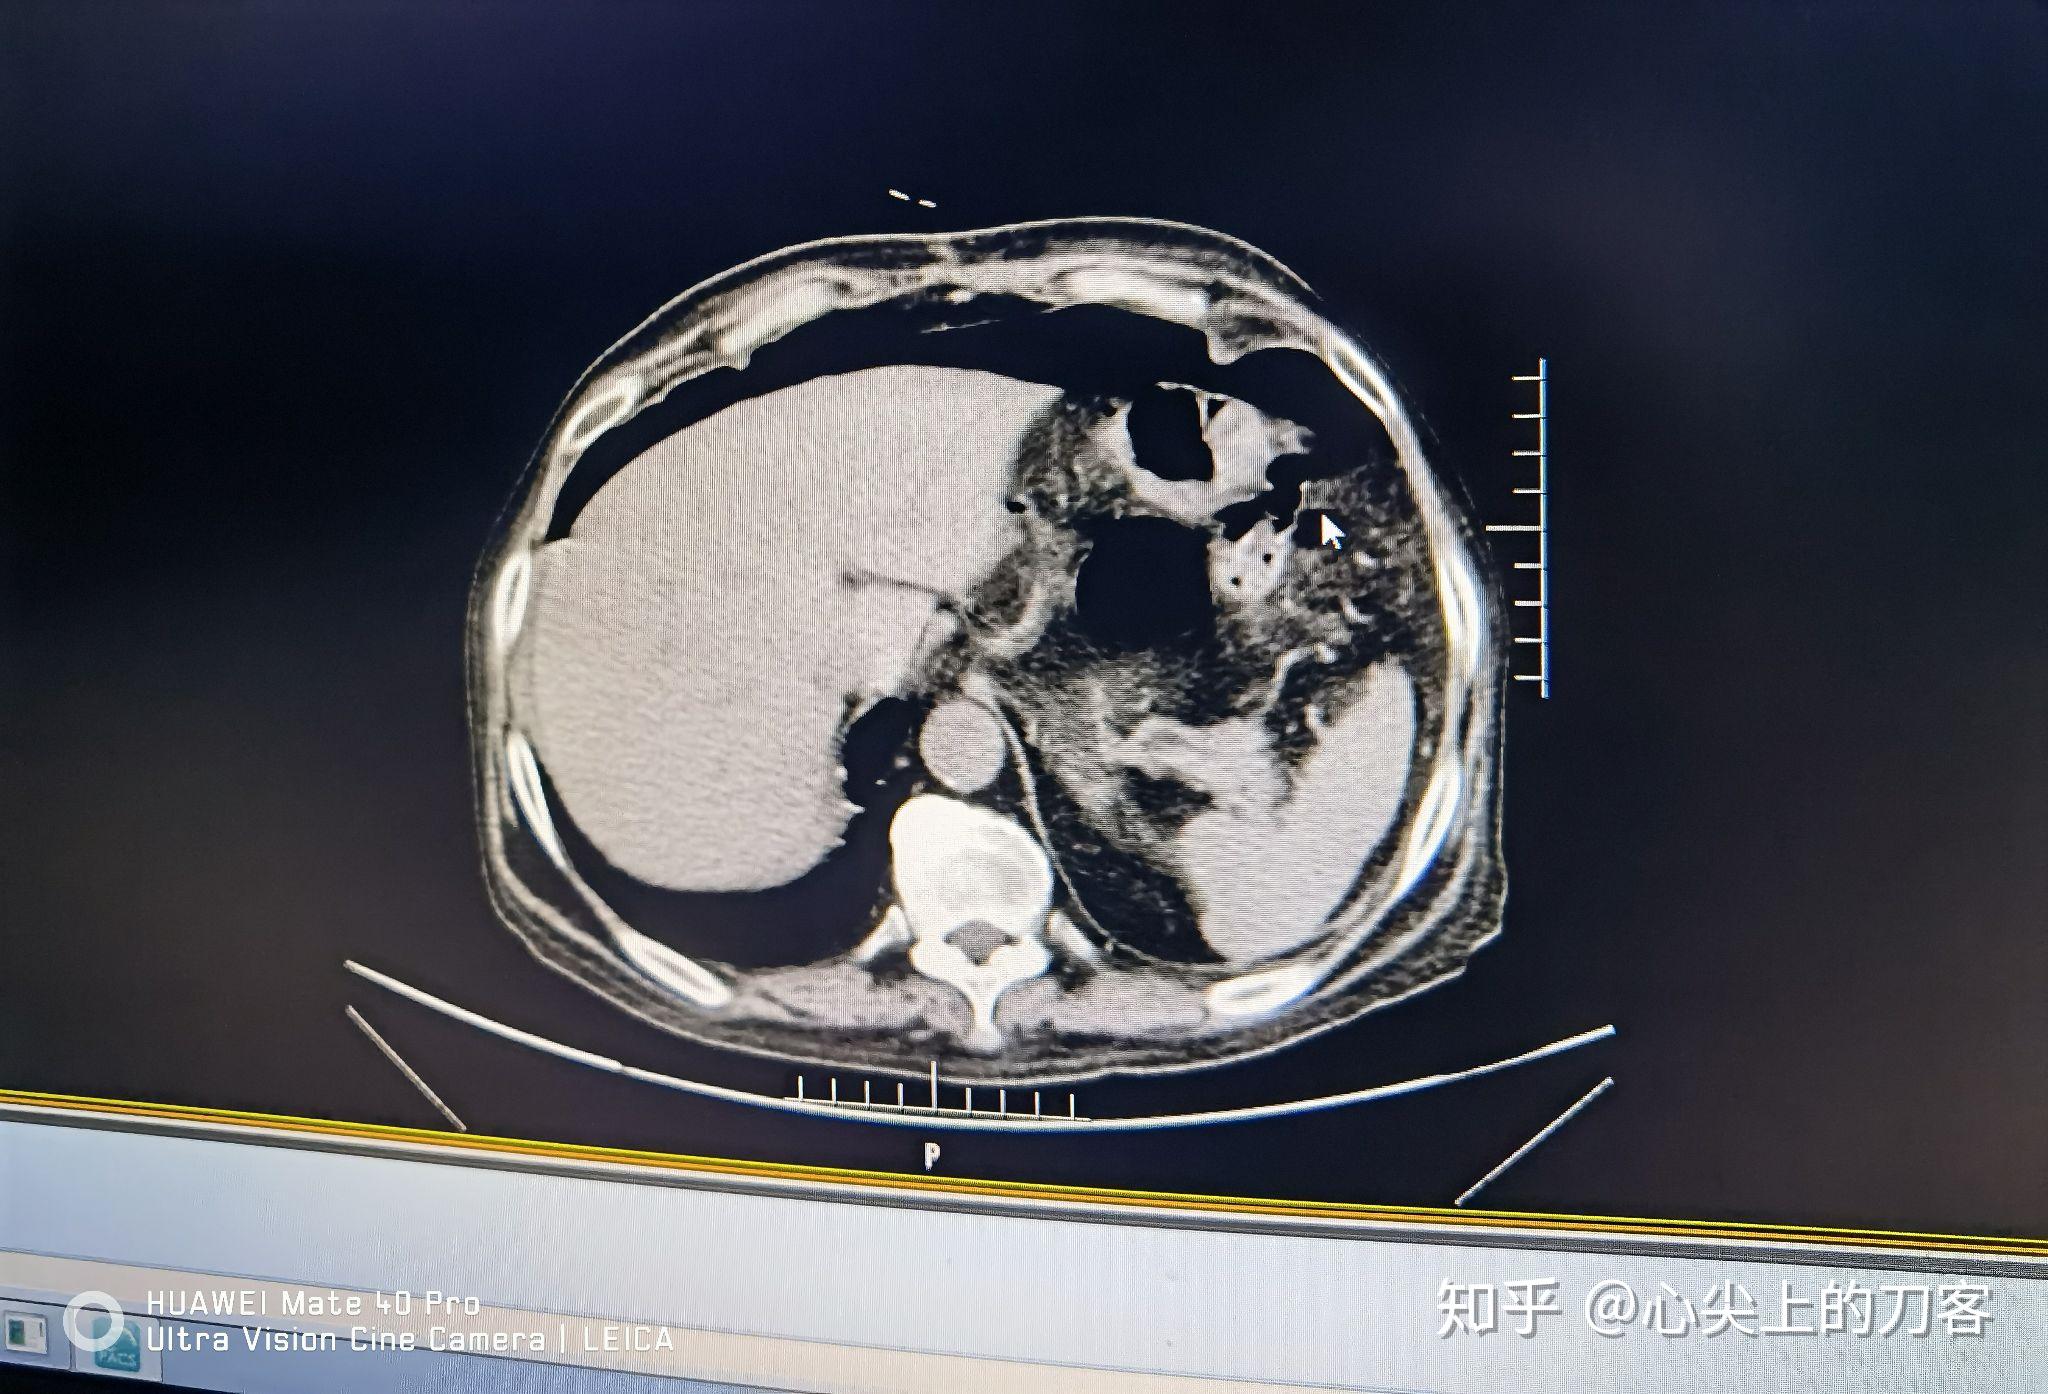

消化道穿孔ct影像大汇总看完印象深刻